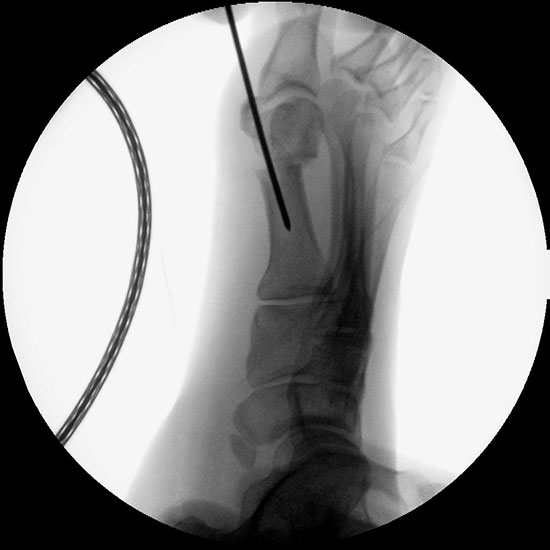

Abbildung 1

• Korrekturpotential größer als beim offenen Chevron, da die Gelenkkapsel als stabilisierendes Element erhalten bleibt und über eine trikortikale Osteosynthese mit zwei kanülierten Schrauben eine Verschiebung bis ca. 80% des Metatarsaledurchmessers möglich ist (Abb. 1).